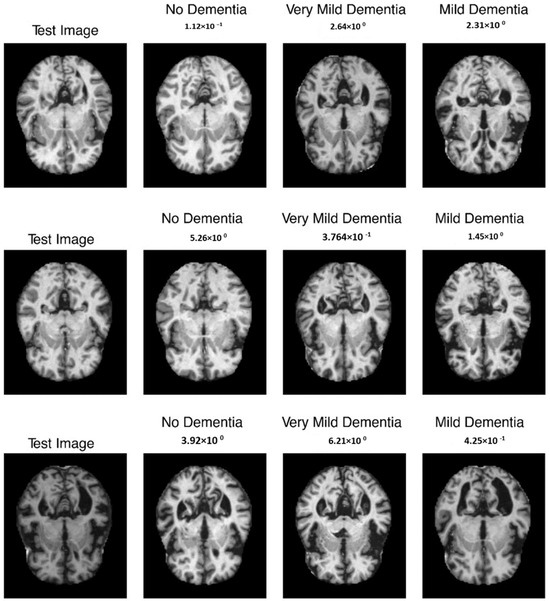

The mean evaluation methods for all patients included 97.5 percent reliability, 96.4 percent sensitivity, and 98.1 percent specificity after sixfold cross-validation. Last but not least, Refs. [34,35] used 2D-CNN techniques to predict both spatial and temporal features of EEG records were used for patient-specific authentication using randomized evaluation metrics. They obtained 91.6 percent selectivity, 90 percent sensitivities, as well as 98.05 percent correctness for the cross-patient information. The sample outcome is shown in Figure 9.

Figure 9.

Sample output with absence, very mild, and mild dementia.

Furthermore, the proposed model enables the customization of the system based on the preferences of physicians or patients by adjusting the relative emphasis on sensitivity and time in warning. Figure 9 illustrates an example application of this adaptable system. Different priorities were selected, including maximizing the improvement over chance (Figure 10a), placing greater importance on high sensitivity by assigning a weight of three to sensitivity compared to time in warning (Figure 10b), and minimizing the duration of the warning state by assigning a weight of three to time compared to sensitivity in warning (Figure 10c). Through a user-friendly interface, a single model parameter can be modified, allowing patients or physicians to easily determine which metric to prioritize and to what extent in real-world scenarios, as depicted in Figure 10.